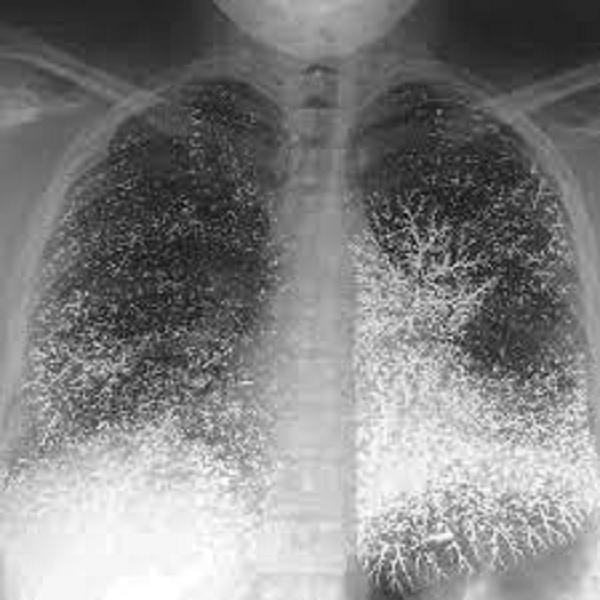

Ngay sau đó, các chuyên gia đã tiến hành mở cỗ quan tài ra và thực hiện 1 cuộc kiểm tra thân phận, cũng như nguyên nhân qua đời của chủ nhân ngôi mộ này bằng sóng điện từ.

Kết quả thu được khiến ai cũng sửng sốt, các bộ phận trên thân thể của chủ nhân ngôi mộ như phần đầu, não bộ, phần ổ bụng hay phần tay đều hiện rõ lên những vùng màu đen và những chấm đen dày đặc. Đặc biệt tại 3 vùng như bụng, tay và xương đều phát hiện 1 lượng lớn thủy ngân.